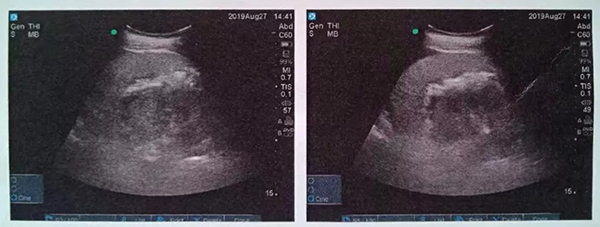

術(shù)中,泌尿外科郭駿博士精心設(shè)計手術(shù)通道,只在患者體表鉆出兩個0.5厘米的小洞,由于患者右側(cè)上位腎位置高,靠近肝臟和肺下葉,容易出現(xiàn)肝臟和肺的損傷,在B超的引導(dǎo)下精確穿刺腎結(jié)石的最高點,逐級擴張后建立皮腎通道。這時屢次“惹禍”的腎結(jié)石清楚的顯露在手術(shù)屏幕上,結(jié)石呈淺黃色,表面覆蓋淺褐色的膿苔,然后使用鈥激光將結(jié)石擊碎后取出。歷時一個半小時,結(jié)石全部清除,手術(shù)結(jié)束。

這種方式是在超聲實時引導(dǎo)下,在腰部經(jīng)皮膚穿刺建立通道(俗稱打洞)進入腎臟,找到腎結(jié)石后用鈥激光碎石。